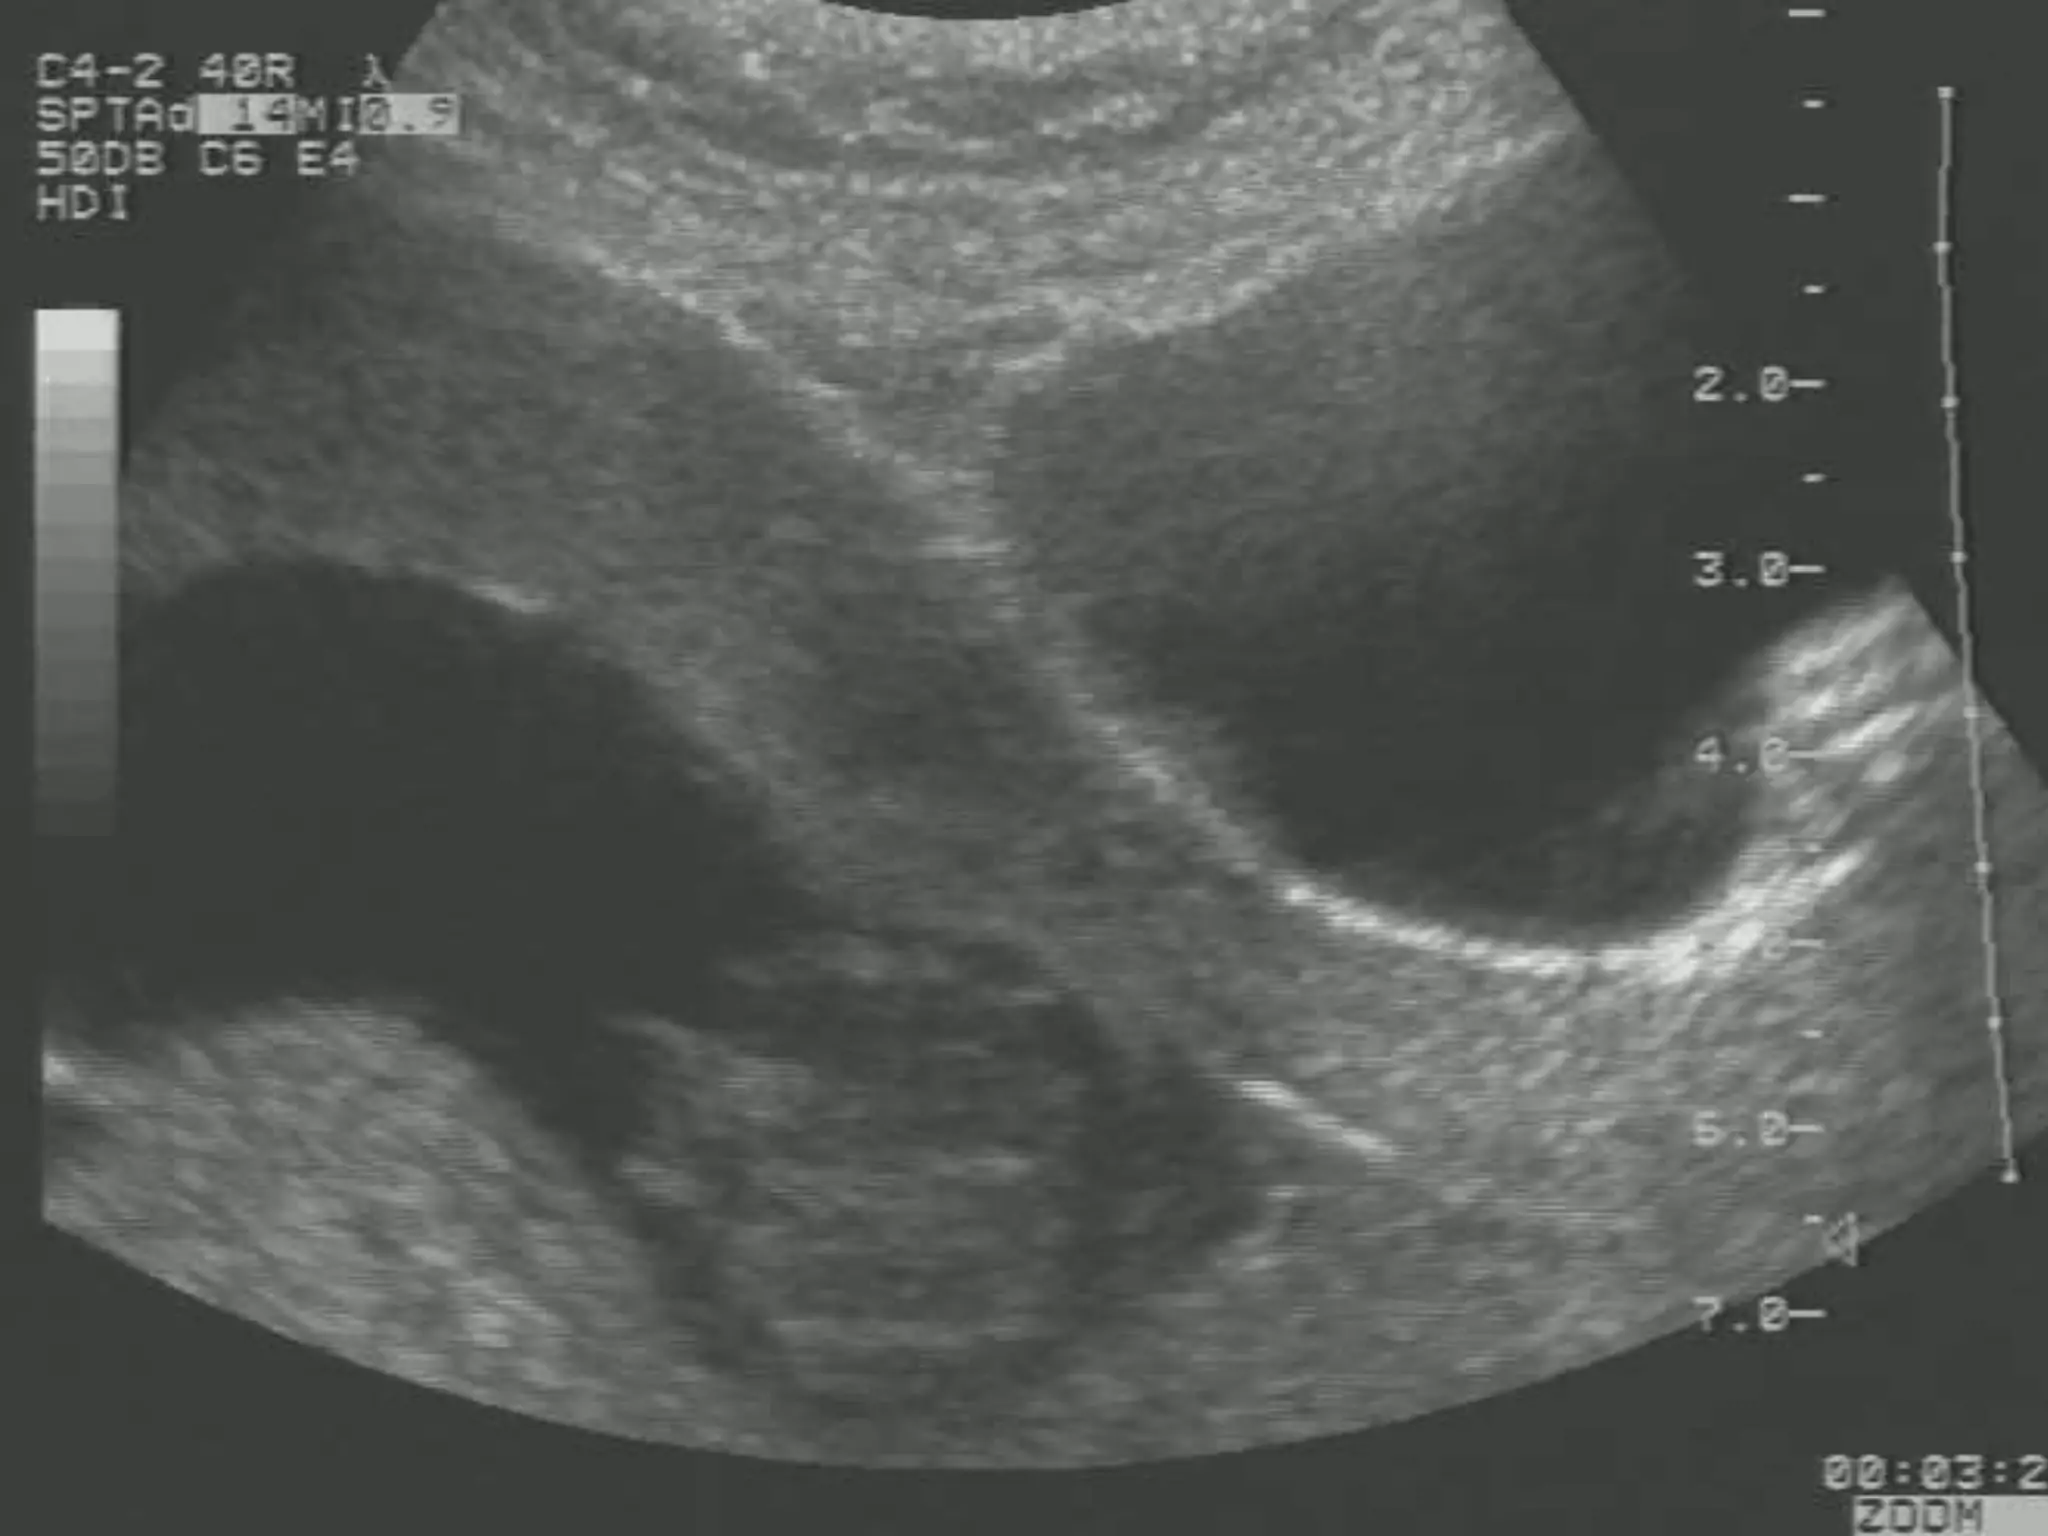

Mid Trimester Amniocentesis

 Per coetaneous

 20-23g needle

 Ultrasound guided

 Usually 20cc amniotic fluid

 Results – 2 to 3 weeks